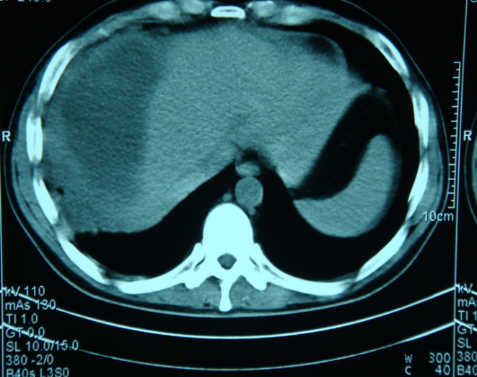

Əməliyyatdaxili ultrasəs müayinəsi 5MHz T tipli linear və ya əyri transdüser ilə aparılır (şək.1)

Transabdominal müayinələrdən fərqli olaraq US gel yerinə normal fizioloji məhluldan istifadə olunur. Ilk olaraq qaraciyər anatomik quruluşu müəyyən edilir (seqmentlər, damarların anatomiyası, öd yollarının variantları və s.) (şək.2)